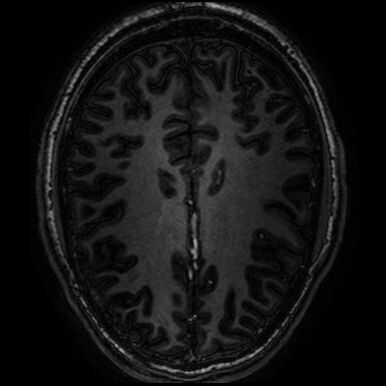

Creo que hay algo sobre una imagen que se generó teniendo cerebro 'rodajas' se imprime en rebanadas - jaja pero en plástico y no cerebro (aunque sería más fácil estudiar!).